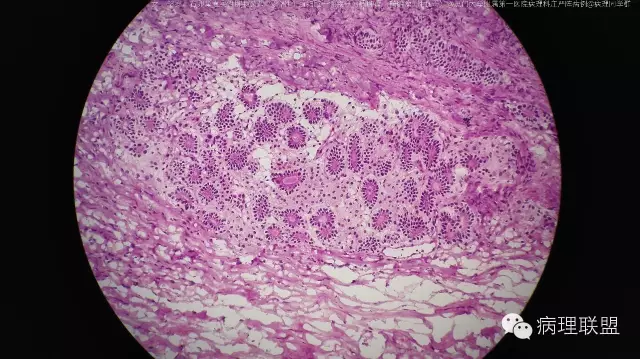

右卵巢囊实性肿物头节-混合性生殖细胞一性索一间质肿瘤(畸胎瘤+性腺母)